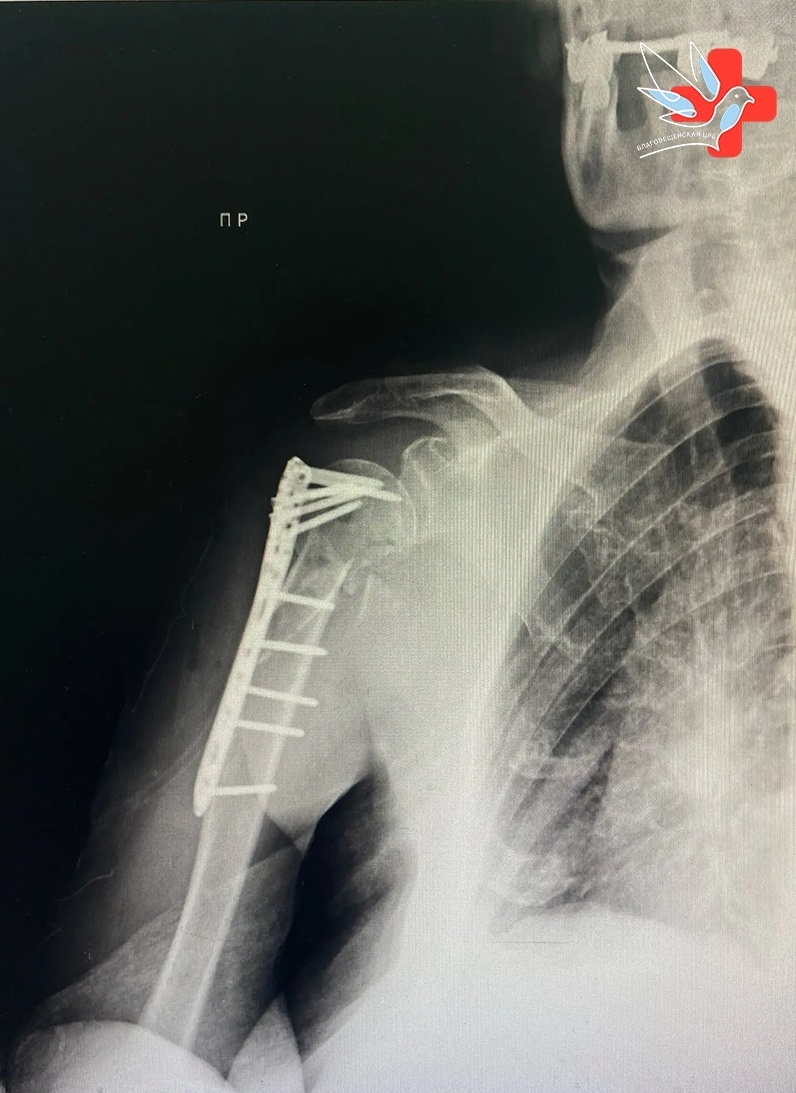

В травматологическое отделение Благовещенской центральной районной больницы была экстренно доставлена 78-летняя женщина после падения дома. Пострадавшая получила серьёзную травму — перелом плечевой кости, что требовало немедленного оперативного вмешательства.

Врач-травматолог Сараж Измайлов успешно провёл сложную операцию — остеосинтез, используя титановую пластину. Благодаря его опыту и слаженной работе всей медицинской команды, пациентка быстро восстановилась и уже выписана домой с положительной динамикой.